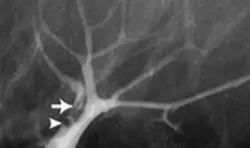

Galaktografi (duktografi) nedir ?

Galaktografi nasıl yapılıyor?